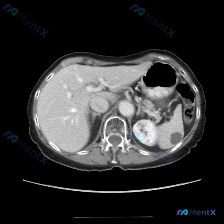

整理了一个近期看到的病例资料和分析思路,分享给大家。 --- 【基本影像信息 - 检查方法: 上腹部CT横断面(软组织窗) - 影像核心表现: - 图像质量良好,解剖结构显示清晰; - 肝脏形态大致正常,肝实质密度尚均匀; - 脾脏:形态饱满,实质内可见较大的类圆形低密度灶,边界尚可辨认,中心密度低...

整理了一个腹部CT的脾脏病灶读片思路,分享一下: --- 先看影像表现 这张是腹部CT软组织窗的横断面: - 肝脏、胰腺、肾上腺、肾脏:这张切面里看到的部分都还好,肝实质均匀,肝缘光滑,肾皮质髓质分界也清,肾上腺区没见明显肿大。 - 脾脏:重点来了,脾脏里能看到一个类圆形的低密度灶。 - 密度:很均...